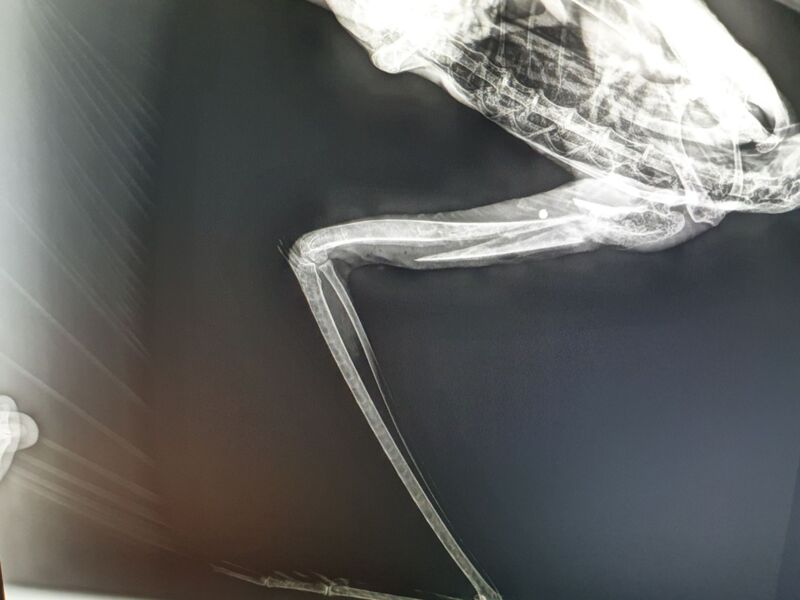

Die Untersuchung bei Tierärztin Ursula Kimberger-Dorninger ergab, dass eine Schrotladung den linken Flügel des zirka sechs Wochen alten Jungvogels zertrümmert hatte. Eine Kugel steckte sogar noch im Körper und wurde herausoperiert.